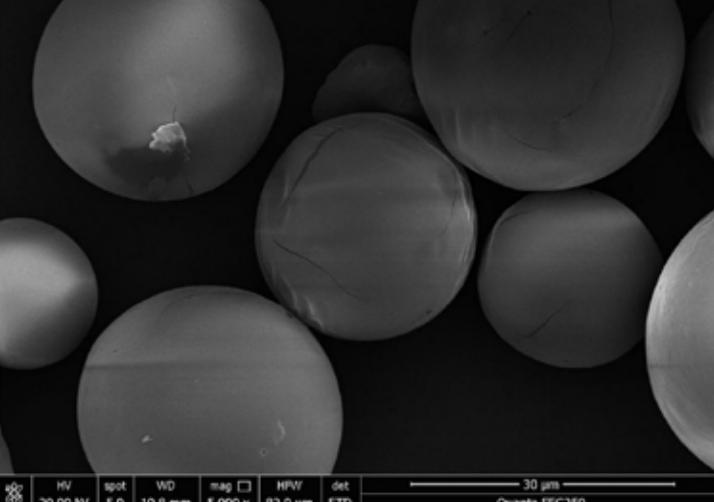

Vita Spire has developed HAp microsphere products for next-generation aesthetic fillers. We offer three different products, each varying in porosity, which corresponds to different degradation rates after injection. Our HAp microspheres provide versatile options for creating specialized, high-quality aesthetic treatments.

| HAPAI-01 | Hydroxyapatite (HAp) Microspheres for Aesthetic Injection, Type I | N/A | Details |

| HAPAI-02 | Hydroxyapatite (HAp) Microspheres for Aesthetic Injection, Type II | N/A | Details |

| HAPAI-03 | Hydroxyapatite (HAp) Microspheres for Aesthetic Injection, Type III | N/A | Details |